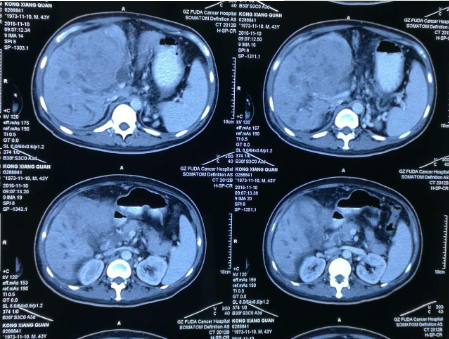

孔祥泉,男性,43岁,因皮肤发黄、肝区不适一个月,各种检查结果很不乐观。MR检查见:“S4/8肝内多发结节及团块(最大102mm*81mm),考虑肝癌合并子灶,侵犯肝门区胆管,门静脉主干及分支、肝右静脉受压、管腔变窄,肝内胆管扩张。胆囊增大并壁周水肿。肝硬化、脾大、少量腹水,食管下段、胃底及脾周静脉曲张,肝门区、门腔间隙及腹主动脉旁淋巴结(百度搜索:广州复大肿瘤医院)。

看到了希望,孔祥泉继续坚持中药调理。两个月之后,孔祥泉再次复诊,他感觉良好,说自己能够每天开车100多公里路往返东莞的公司上班,兴高采烈地说自己恢复正常了!并且实验室检查结果也显示,除了AFP增高之外,其他指标都基本正常。看到这样的结果,我们科所有的人都替他感到高兴!

十个月后,大家的努力,终于迎来了患者的健康。

确诊晚期肝癌的孔祥泉先生,从徐院长给他实施中药治疗到现在,存活了整整十个月,远远超过当初中山大学附属肿瘤医院预计的三个月的生命期限。最重要的是现在病人精神状态和自我感觉都很好,可以正常工作,各项生化指标基本都趋于稳定。